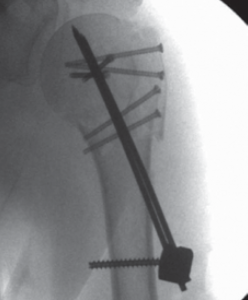

Hierbei werden unterschiedliche Implantate zur Stabilisierung des Knochenbruches in Abhängigkeit vom Frakturtyp verwendet. So können Frakturen entweder mittels Drähten, Schrauben, Platten oder Marknägeln stabilisiert werden.

Vielfach lassen sich teilweise auch komplexe Oberarmkopffrakturen minimal-invasiv versorgen. Dabei gelingt es über kleine Hautschnitte die verschobenen Fragmente wieder aufzurichten und mittels Humerusblock sowie zusätzlichen Schrauben die Fraktur zu stabilisieren (Abb. 53 bis 55). Neben der gewebeschonenden Versorgung stellt auch das günstige kosmetische Ergebnis einen entsprechenden Vorteil dar.